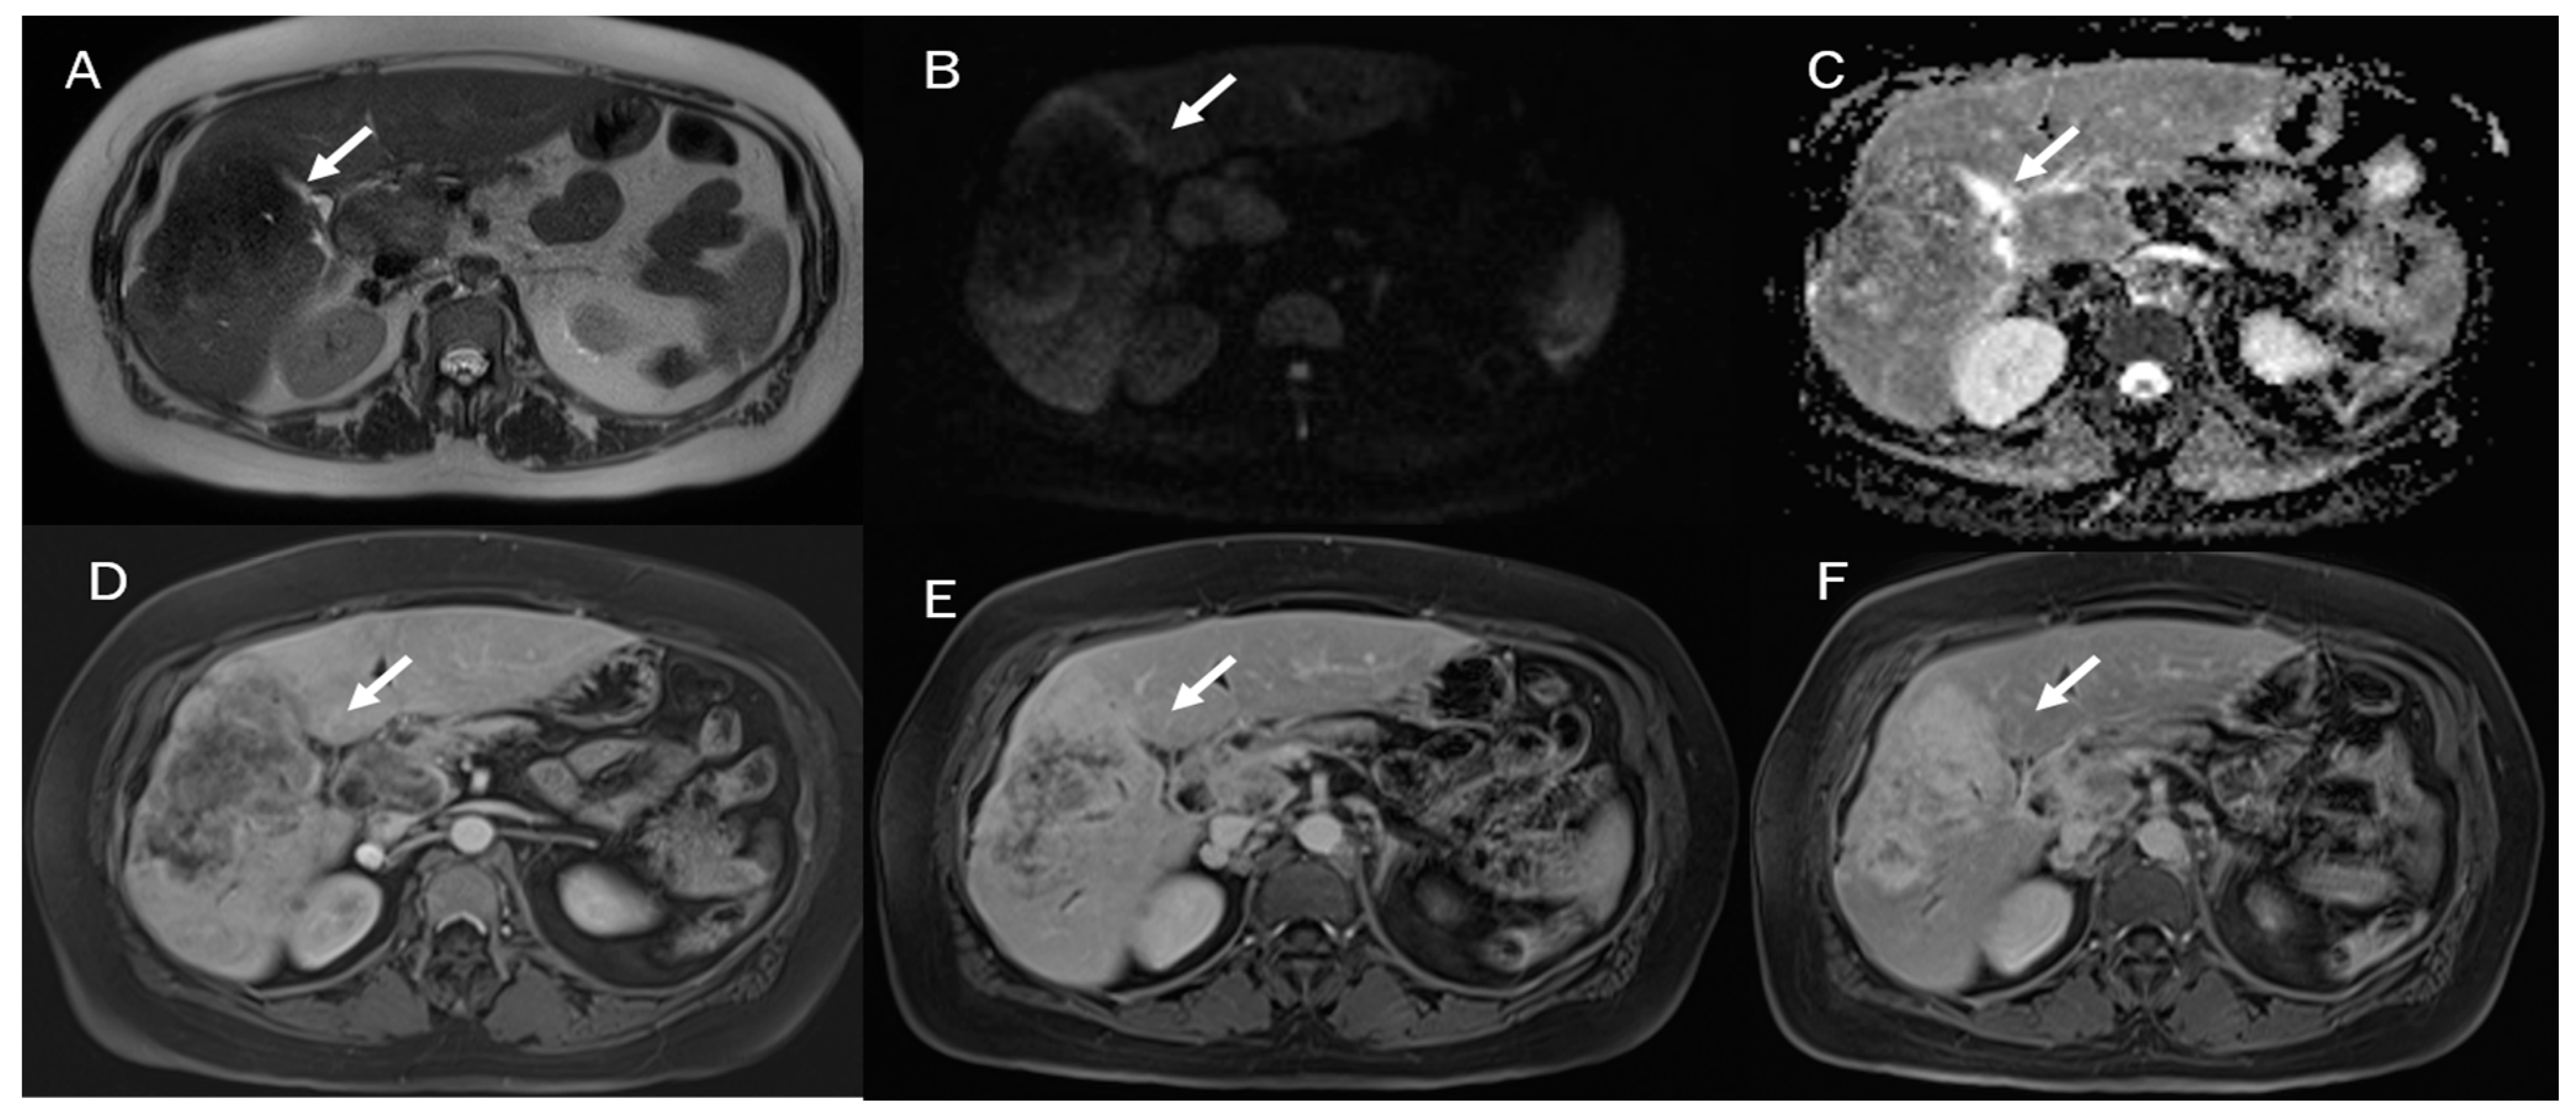

In MRI imaging, ICC presents typical features as capsular retraction adjacent to the tumor. In T1-W sequences, the lesion appears with a targetoid aspect or hypointense signal. While most of the lesions also appear targetoid (Figure 5) in T2 sequences, some can show hyperintense signals. After contrast administration in the arterial phase in ICC, it is possible to identify the peripheral rim hyperenhanced. In the portal phase, the lesion slowly increases its entire enhancement (Figure 5 and Figure 6) [181,182,183,184].

Figure 5.

ICC MRI assessment. The lesion (arrow) shows hypointense signal in T2-W sequence (A) due to fibrotic tissue, with targetoid appearance in DWI (B) and ADC map (C) and progressive contrast enhancement during arterial (D), portal (E), and delay (F) phases of contrast study.

Figure 6.

MRI assessment of periductal-infiltrating CCA. The lesion (arrow) shows hyperintense signal in T2-W (A), causing biliary tree dilatation in cholangiography sequences (B). During arterial phase (C), the lesion causes hyperenhancement of surrounding liver parenchymal, showing a progressive contrast enhancement in portal phase (D).